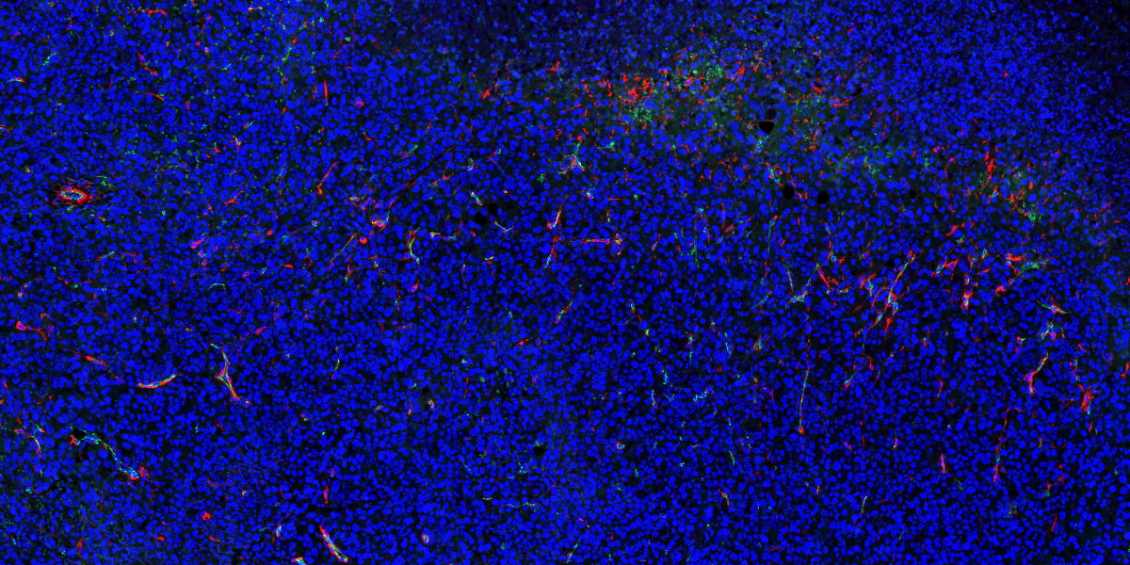

黑龙江石蜡切片免疫荧光不可避免会产生自发荧光。

1.取材的时候灌注取材,把红细胞冲洗干净;

2.脱蜡必须彻底,封闭、洗涤等过程也需充分;

3.抗体在使用前最好先离心处理并尽量从上方吸取,抗体的浓度过高也会产生自发荧光,所以可以预实验摸清最合适的抗体浓度再进行正式实验;

4.如若自发荧光很强,严重影响染色效果,亦可采用自发荧光去除剂进行去除。